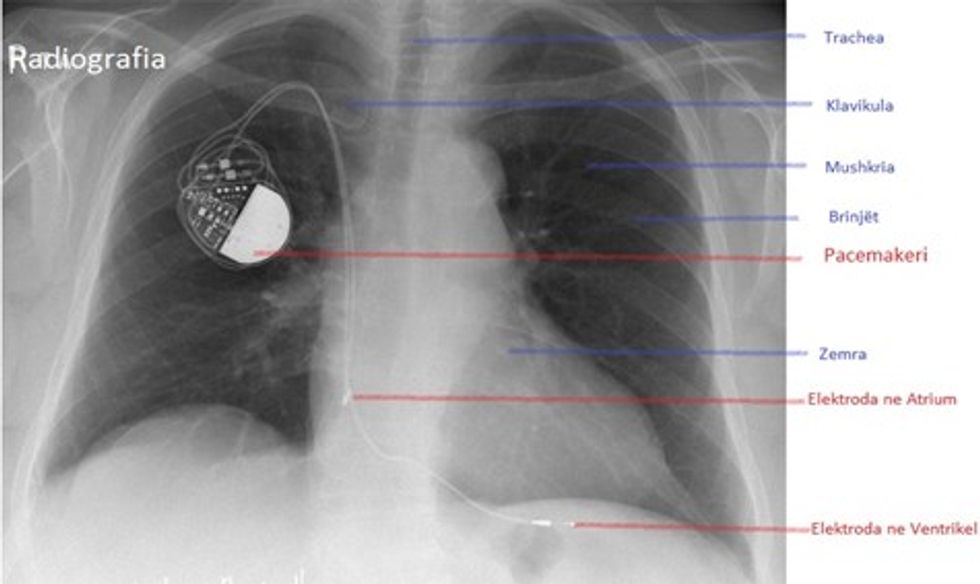

Pacemakerët përbëhen nga një baterie, një qendër që ka funksionin e nyjës atriale, të cilat janë të vendosura në një kuti metalike dhe Sondat (elektrodat, fije teli) që vendosën nëpër një enë të gjakut (venë) në zemër. Përmes këtyre telave Pacemaker jep informacionin në rast nevoje direkt në zemër dhe si pasojë e kësaj zemra kontraktohet dhe punon si pompë në mënyrë të rregullt.

Pacemakeri vendoset zakonisht nën klavikulë, në anën e majtë apo të djathtë të gjoksit. Nën një anestezion lokal bëhet një prerje e lëkurës me një gjatësi rreth 3 cm. Përmes enës së gjakut (venës) vendosen elektrodat (telat) varësisht nga nevoja një apo dy direkte në zemër. Vendosja e elektrodave bëhet nën rrezet rëntgen duke u parë në një ekran. Ato fiksohen në muskulaturë të zemrës dhe bëhet matja e tyre. Këto elektroda konektohen, pastaj në Pacemaker. Pacemaker së bashku me elektroda vendosën nën muskulaturë. Pas vendosjes së Pacemakerit, bëhet programimi i tij për secilin pacient individualisht. Gjatë gjithë operacionit, pacienti është i zgjuar, komunikon dhe nuk ka dhimbje, përpos një gjilpëre që në fillim kur i jepet medikamenti kundër dhimbjeve.